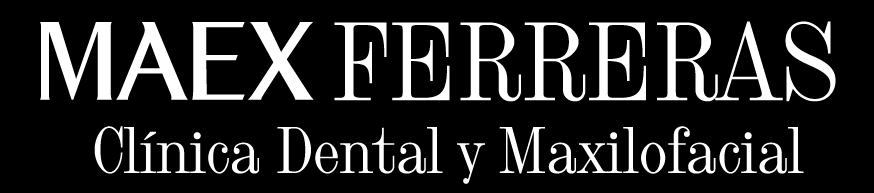

Software de planificación

Software de planificación para la colocación de implantes dentales tras injerto de cresta ilíaca.

Software de planificación para la colocación de implantes Zigomáticos (Zigoma Quad).